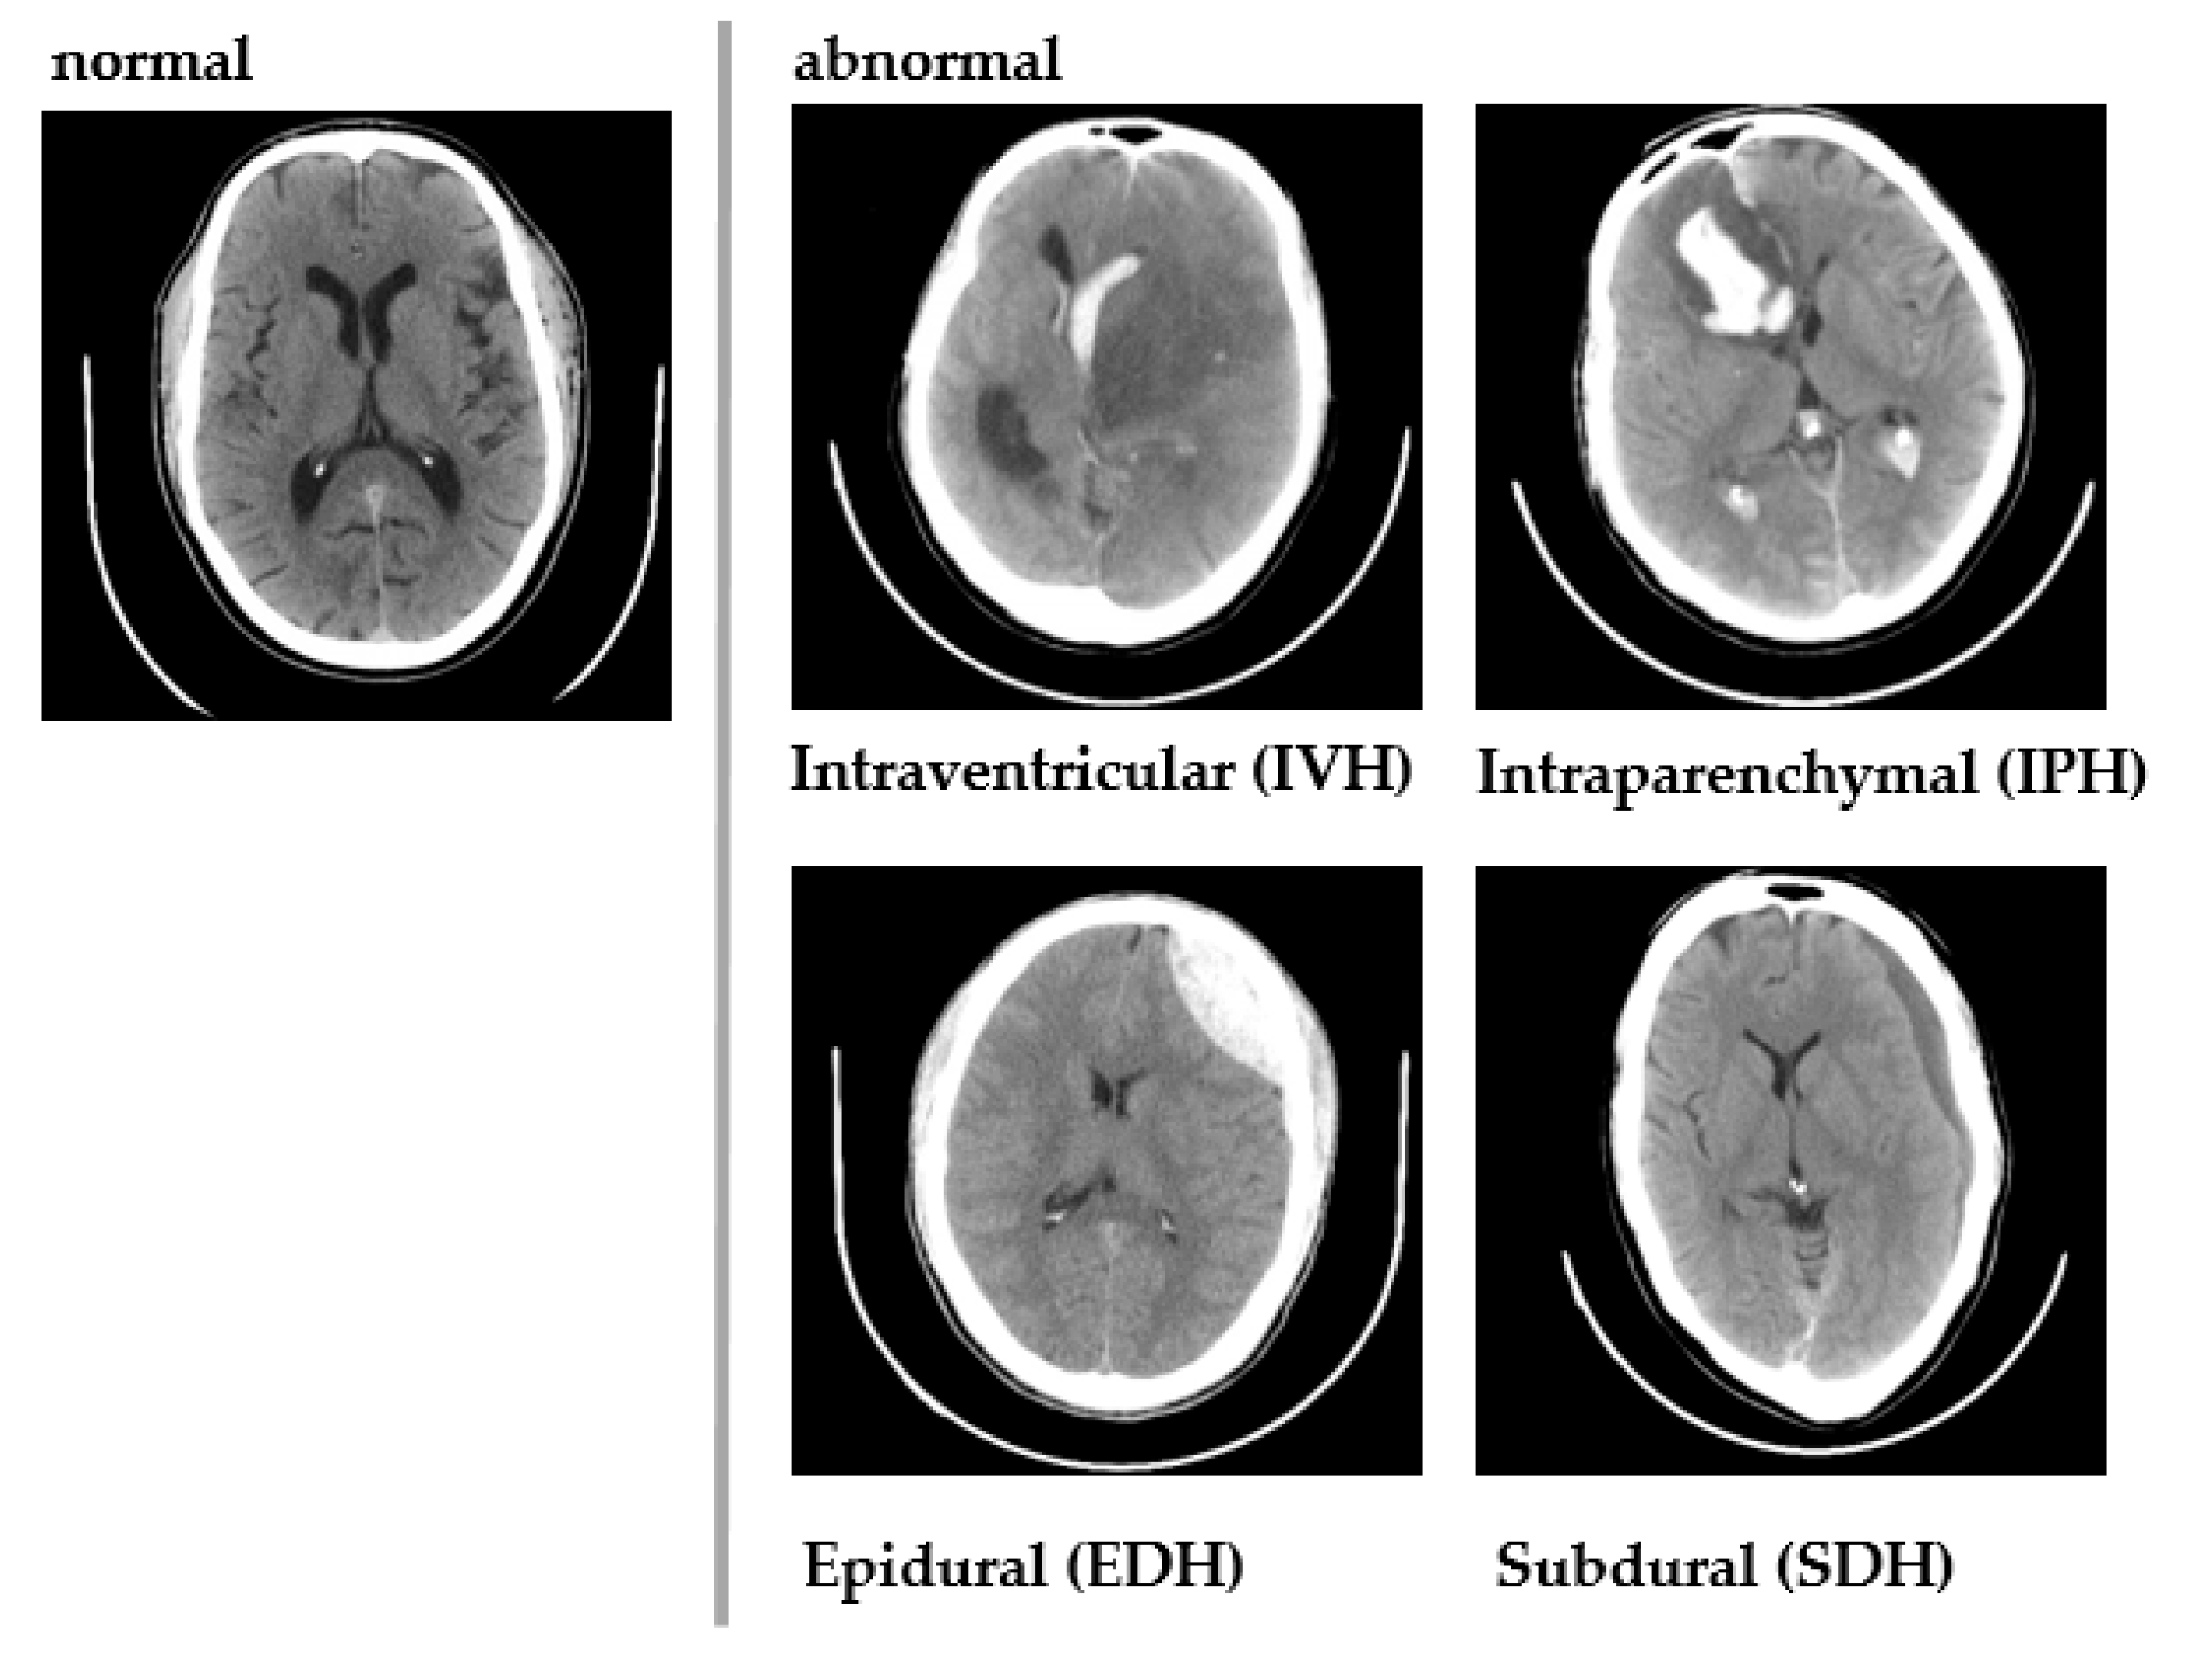

1. Introduction

3.2. RSNA Dataset